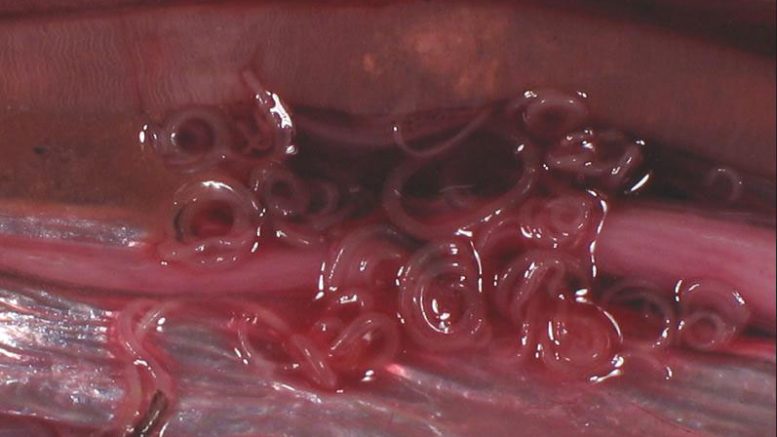

L’anisakis è un nematode (verme) parassita che si annida nelle pareti dello stomaco. Il pesce e i crostacei sono le principali fonti di contagio: l’uomo mangiando pesci, o calamari crudi o poco cotti, può ingerire le larve dei nematodi, responsabili di una malattia nota come anisakidiosi. Le larve ingerite spesso muoiono o non danno sintomi. In alcuni casi però possono invadere la mucosa gastrica o intestinale e causare dolori addominali, nausea, vomito ed occasionalmente febbre. Una volta penetrate nella mucosa ne deriva una reazione infiammatoria che può evolvere fino a causare ulcere (fonte: IZS Veneto).